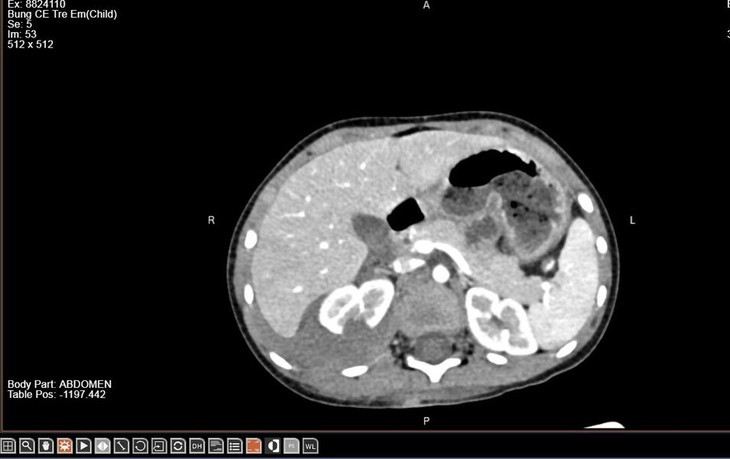

Trẻ được chỉ định thực hiện chụp cắt lớp vi tính ổ bụng có tiêm thuốc cản quang để đánh giá mức độ tổn thương thận. Kết quả cho thấy thận phải vỡ làm 2 mảnh, có thoát thuốc ra khoang quanh thận. Bác sĩ kết luận trẻ bị chấn thương thận phải độ IV theo ASST (bảng phân loại chấn thương thận của Hiệp hội Phẫu thuật Chấn thương Mỹ).

Hình ảnh vỡ thận trên phim chụp - Ảnh BVCC